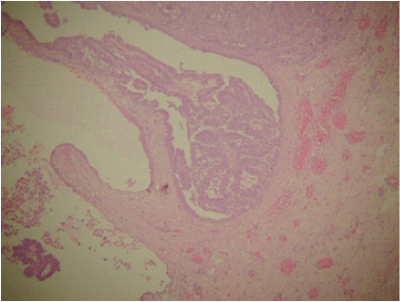

Histology analysis of the specimen showed poorly differentiated adenocarcinoma of endometrioid type, arising from the left fallopian tube with metastatic spread to ovaries, peritoneum and the appendix epiploicae as shown in the Figures 1–3. No metastatic spreads were found in the omentum. The cytology of the ascites was positive for adenocarcinoma cells. FIGO staging was of fallopian tube tumour stage IIB.

Figure 1 Fallopian tube carcinoma.